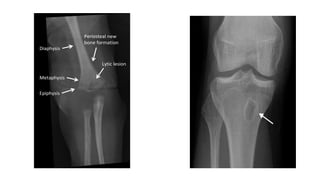

• X-ray:- a lytic focus of bone destruction surrounded by a zone of sclerosis is characteristic radiographic

finding.

Parts of a young bone

• Epiphysis:- End of bone, ossifies

from secondary center of

ossification.

• Diaphysis:- Shaft of a long bone,

ossify by primary center of

• Metaphysis:- epiphyseal end of

diaphysis, zone of active growth.